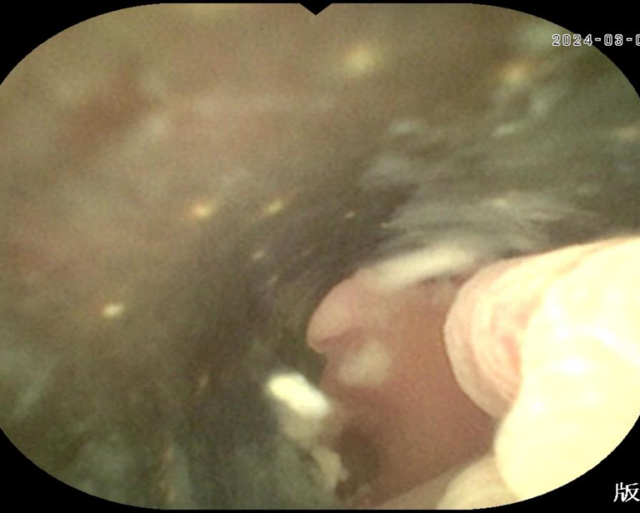

术中利用无痛肠镜技术到达阑尾开口,采用最新的“eyeMAX洞察”子母镜系统直视下进入阑尾腔内,通过冲洗、引流、网篮套取等操作,将嵌顿于阑尾腔内的粪石取出,术后患者腹痛明显缓解,1h后即可下地行走。次日顺利出院。

据徐宏伟主任介绍:内镜下逆行性阑尾炎治疗术是一种新型的内镜技术,经肠镜达到阑尾开口处,通过子母镜系统将超细的内镜探头置入阑尾腔内,直视下观察阑尾内部情况,并通过相关的器械(导管、网篮、支架等)对阑尾内的脓液、粪石进行处理,解除阑尾的梗阻,清除阑尾的炎症,是阑尾炎治疗的一种新型方式,相比外科手术而言,有着以下三大特点: